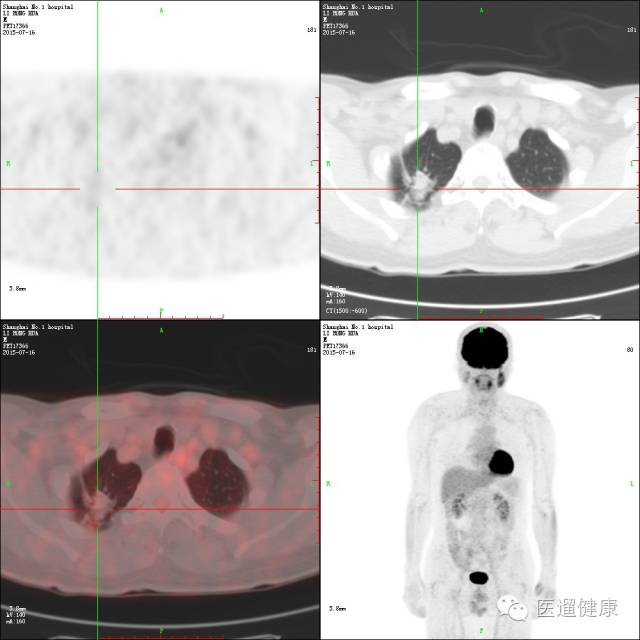

案例三

68岁男性,既往有前列腺癌病史。胸部CT:左肺下叶周围型肺癌;T9骨病灶,转移可能。

临床医生意见:

1)肺病灶是原发的,还是转移的?2)如果胸骨病灶是前列腺癌来源的骨转移灶,而肺占位是原发的话,可以对左肺占位进行手术。

困难所在:

如何鉴别胸骨病灶是前列腺癌转移来的,还是肺癌转移来的?

2013年6月24日PET/CT:

1. 盆底多发囊性病灶伴囊壁结节状葡萄糖代谢增高,考虑囊腺性肿瘤。(此后病理证实为前列腺癌)

2. 双侧髂血管旁多发淋巴结肿大,多发性骨病灶,葡萄糖代谢均增高,考虑肿瘤多发转移灶。

3. 乙状结肠结节伴葡萄糖代谢增高,考虑腺瘤可能,建议肠镜协诊。

4. 左肺下叶外基底段结节,葡萄糖代谢未见异常,建议随访。

2015-7-16PET/CT:

通过前后对比分析,判定了骨转移灶来自前列腺癌,左下肺病灶为原发性肺癌,可做肺癌切除手术。